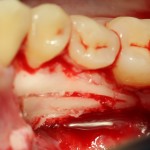

Костная «дверца» на время отделяется и убирается в физраствор, а мы видим следующее:

Это фолликулы и, частично, коронковые части сверхкомплектных зубов.

Теперь аккуратно нам нужно выделить сами зубы:

А вот они! Далее мы руководствуемся главным правилом хирурга-стоматолога: